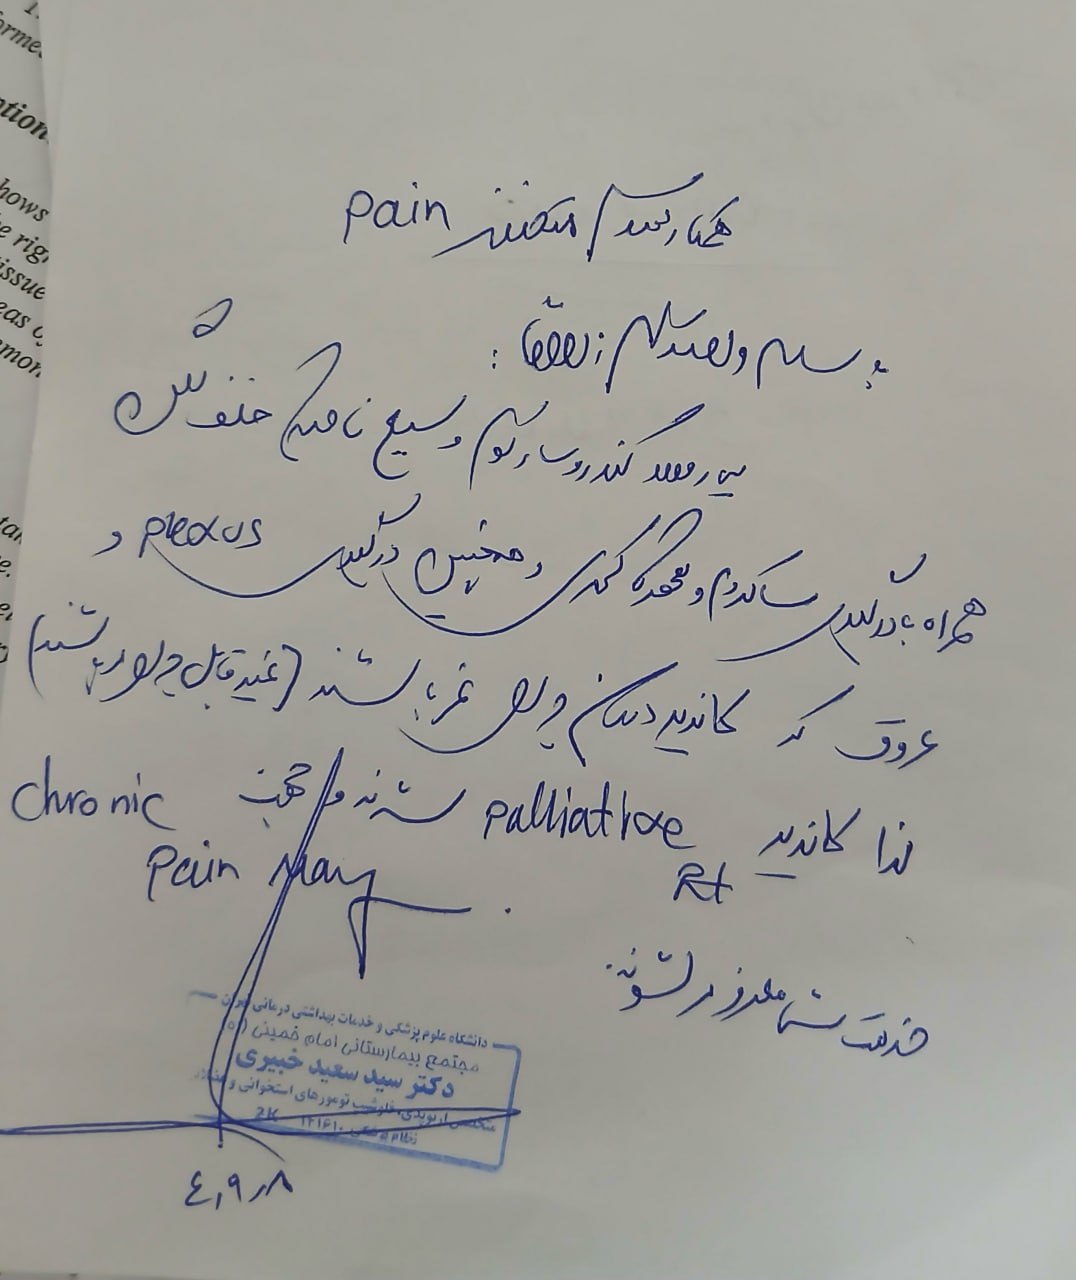

بیمار سابقه درد لگن مقاوم به درمان داشته بهطوری که مصرف متادون و مورفین تأثیر قابل توجهی بر کنترل درد نداشته است.

از نظر علائم عصبی، بیمار گزگز اندام تحتانی چپ را ذکر میکند. ضعف واضح یا اختلال در کنترل ادرار و مدفوع گزارش نشده است. یبوست مقاوم یا احساس فشار رکتال وجود نداشته است.

مراجعه کرده است. پس از بررسی های انجام شده در MRI انجام شده توده با درگیری مفصل ساکروایلیاک چپ و DVT؛ ابتدا تحت درمان DVT قرار گرفته است و سپس جهت پیگیری تومور رویت شده تحت بیوپسی قرار گرفته است و با تشخیص کندروسارکوما به این مرکز مراجعه کرده است و تحت کموتراپی و رادیوتراپی قرار گرفته و سایز تومور کاهش یافته است.

(تصویر مربوط به این مراجعه نیست) Other:

(تصویر مربوط به این مراجعه نیست) Other:

(تصویر مربوط به این مراجعه نیست) Other:

(تصویر مربوط به این مراجعه نیست) Other:

(تصویر مربوط به این مراجعه نیست) Other:

(تصویر مربوط به این مراجعه نیست) Other:

(تصویر مربوط به این مراجعه نیست) Other:

(تصویر مربوط به این مراجعه نیست) Other:

(تصویر مربوط به این مراجعه نیست) Other:

(تصویر مربوط به این مراجعه نیست) Other:

(تصویر مربوط به این مراجعه نیست) Other:

(تصویر مربوط به این مراجعه نیست) Other:

(تصویر مربوط به این مراجعه نیست) Other:

(تصویر مربوط به این مراجعه نیست) Other:

(تصویر مربوط به این مراجعه نیست) Other:

(تصویر مربوط به این مراجعه نیست) Other:

(تصویر مربوط به این مراجعه نیست) Other:

(تصویر مربوط به این مراجعه نیست) Other:

(تصویر مربوط به این مراجعه نیست) Other:

(تصویر مربوط به این مراجعه نیست) Other:

(تصویر مربوط به این مراجعه نیست) Other:

(تصویر مربوط به این مراجعه نیست) Other:

(تصویر مربوط به این مراجعه نیست) Other:

(تصویر مربوط به این مراجعه نیست) Other:

(تصویر مربوط به این مراجعه نیست) Other:

(تصویر مربوط به این مراجعه نیست) Other:

(تصویر مربوط به این مراجعه نیست) Other:

(تصویر مربوط به این مراجعه نیست) Other:

(تصویر مربوط به این مراجعه نیست) Other:

(تصویر مربوط به این مراجعه نیست) Other:

(تصویر مربوط به این مراجعه نیست) Other:

(تصویر مربوط به این مراجعه نیست) Other:

(تصویر مربوط به این مراجعه نیست) Other:

(تصویر مربوط به این مراجعه نیست) Other:

(تصویر مربوط به این مراجعه نیست) Other:

(تصویر مربوط به این مراجعه نیست) Other:

(تصویر مربوط به این مراجعه نیست) Other:

(تصویر مربوط به این مراجعه نیست) Other:

(تصویر مربوط به این مراجعه نیست) Other:

(تصویر مربوط به این مراجعه نیست) Other:

(تصویر مربوط به این مراجعه نیست) Other:

(تصویر مربوط به این مراجعه نیست) Other:

(تصویر مربوط به این مراجعه نیست) Other:

(تصویر مربوط به این مراجعه نیست) Other:

(تصویر مربوط به این مراجعه نیست) Other:

(تصویر مربوط به این مراجعه نیست) Other:

(تصویر مربوط به این مراجعه نیست) Other: